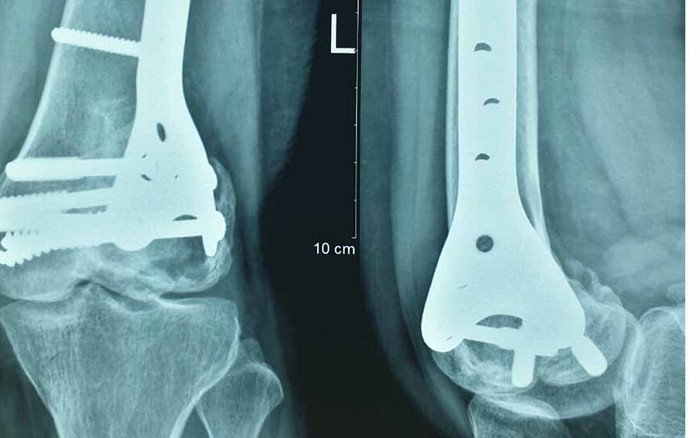

5. Đục xương sửa trục

- Đục xương sửa trục thực chất là thay đổi trục cơ học của chân, thay đổi trọng tâm chịu lực của khớp gối, giảm áp lực lên bề mặt khớp thoái hóa, qua đó giúp bệnh nhân giảm đau và làm chậm quá trình thoái hóa. Phương pháp này thường chỉ định đối với thoái hóa khớp gối sớm, một khoang, hay gặp ở bệnh nhân có biến dạng chân kiểu vẹo trong hay vẹo ngoài. Tuy nhiên phương pháp này có thể gặp tai biến nghiêm trọng là liệt dây thần kinh mác chung. Ngoài ra, về lâu dài nếu bệnh nhân cần thay khớp sẽ phải đối mặt với vấn đề trục chi đã bị thay đổi.

6. Thay khớp gối

- Thay khớp gối được áp dụng khi bệnh đã ở giai đoạn 3 hoặc 4, không thể điều trị bằng các phương pháp khác. Tuy nhiên đây là phẫu thuật lớn, chi phí bỏ ra rất cao. Thêm vào đó, tuổi thọ của khớp nhân tạo chỉ khoảng 10 - 15 năm, nên với bệnh nhân trẻ tuổi sẽ phải đối mặt với nguy cơ thay lại khớp nhiều lần. Do đó với phương pháp này, bệnh nhân sẽ được bác sĩ chuyên khoa khám xét và tư vấn kỹ lưỡng.